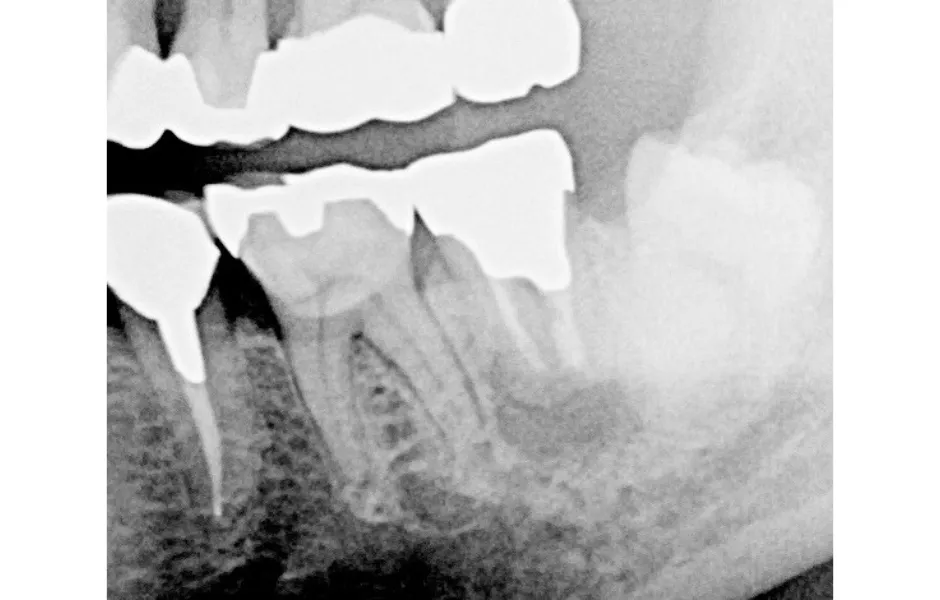

精密根管治療

神経まで進行して炎症を起こしている虫歯に対して行なう治療法になります。感染した神経を取り除き、しっかりと洗浄・消毒し、最後に薬剤を詰めて被せ物を装着します。

精密根管治療 -